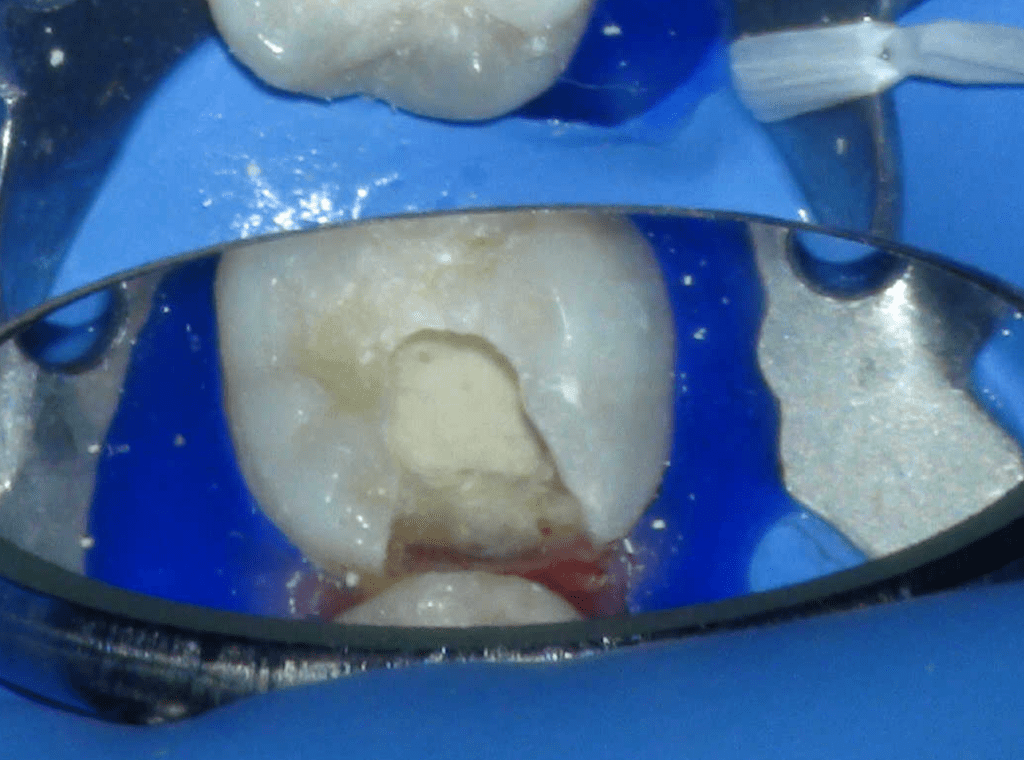

Reconstrucción preendodóntica

Reco pared vesticular